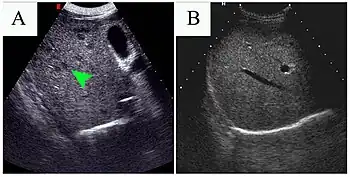

| a-c)Sonography images of male child diagnosed with hepatic visceral larva migrans | |